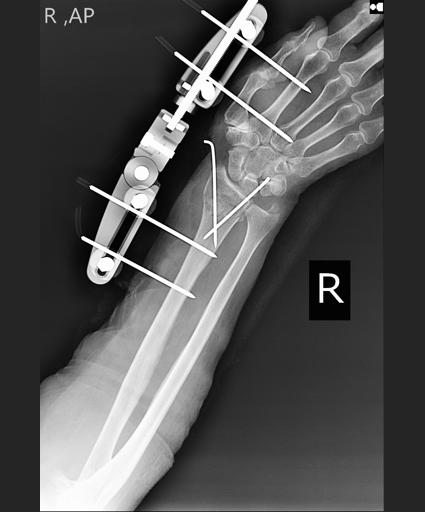

Our startup company specializes in providing anatomically designed and adjustable external fixators tailored to address prevalent orthopedic injuries. Our flagship products, the Anatomic Dynamic Distal Radius External Fixator and the Anatomic Dynamic Hip External Fixator, offer innovative solutions backed by US patents.

An External Fixator is a stabilizing frame designed to maintain proper alignment of fractured bones. This device involves the insertion of metal pins or screws through small incisions in the skin and muscle, with these pins and screws then affixed to an external bar. External Fixators are commonly employed in cases of severe traumatic injuries, providing swift stabilization while facilitating access to soft tissues that may require concurrent treatment. This is especially crucial in instances of substantial damage to the skin, muscle, nerves, or blood vessels. Additionally, External Fixators are utilized for fractures requiring distraction (Ligamentotaxis), bone reconstruction, and specific types of bone fractures.

From historical point of view, early designs for internal fracture fixation devices relied on crude and limited elements that needed to be adapted for each fracture type. However, with the advent of locking plates and the conduction of anatomic studies focusing on the articular ends of long bones, anatomic plates emerged, sparking a revolution in orthopedic surgery. These plates can be utilized in a minimally invasive manner, boasting a smaller profile and a more robust fixation compared to traditional articular plates. By adhering to the 'anatomic' principle, these plates match the native anatomy without necessitating intraoperative contouring, thus saving valuable time during lengthy procedures. Considering this historical progression in internal fracturefixation, our current concept extends to achieving similar advancements in anatomic external fixators. These fixators can be customized to adjust the unique anatomy of each patient, thereby facilitating a more precise reduction of fracture fragments and promoting patient outcomes.